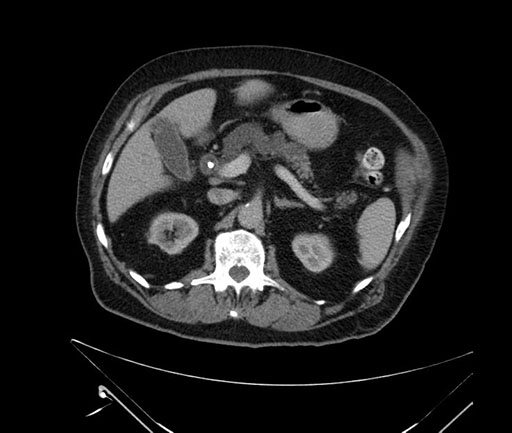

Whipple (pancreaticoduodenectomy) [case 7]

Imaging Analysis

Look through the patient's CT scan to identify any areas of concern for the necessary procedure.

Based on your CT findings, which issue(s) would give reason for "planned slowing down moment(s)" in this case?

Considering a standard Whipple procedure, what step(s) of the operation would you do differently in this case?